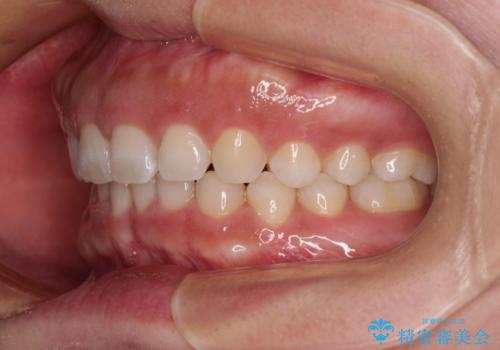

【モニター】ディープバイトを治す ワイヤー装置による矯正治療

- 顎が疲れるほどのディープバイトを気にして来院された患者様です。

手前に傾斜している奥歯を直立させながら、歯列全体の平面を均一に整えることでディープバイトを改善していくこととしました。

ディープバイトは咬合力が強いことが特徴であり、より良い仕上がりとするために、臼歯部のコントロールを行いやすいワイヤー装置を用いて矯正治療を行うこととしました。

ディープバイトが改善されたことで、食いしばりしかできなかった状態からスムーズな歯ぎしりができるようになりました。